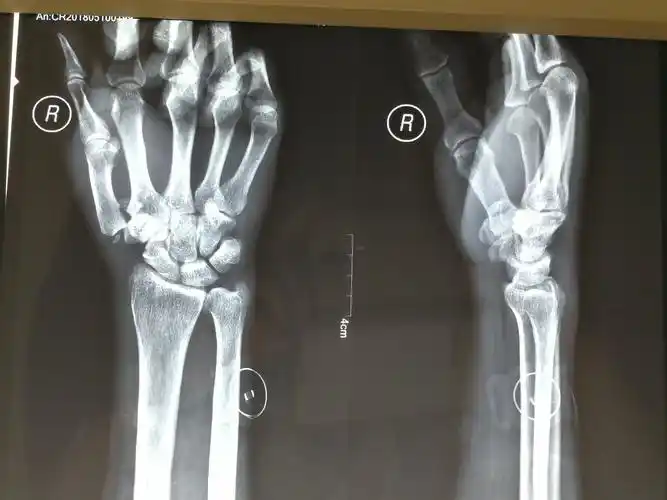

本耐氏bennett骨折即第一掌骨基底部骨折伴脱位